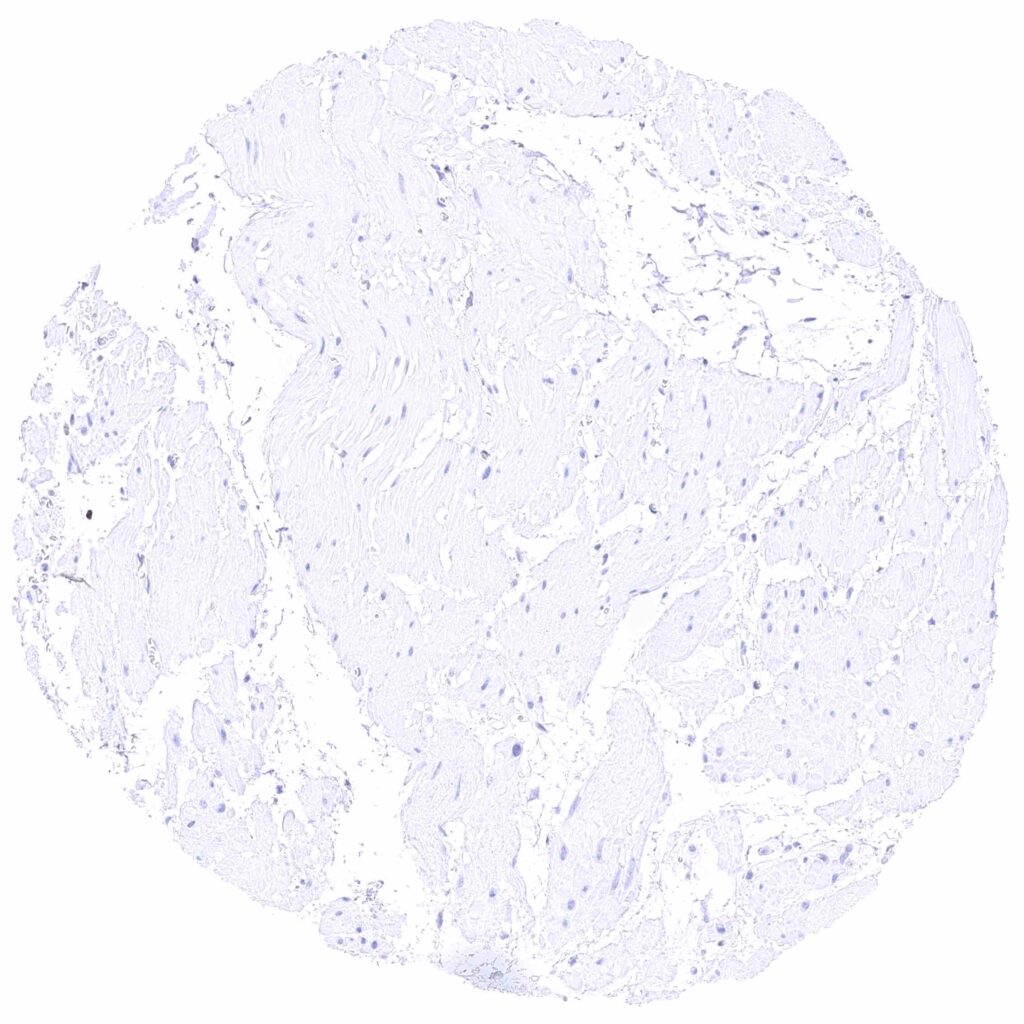

Esophagus, muscular wall

Colon descendens, muscular wall

Appendix, muscular wall

Ileum, muscular wall